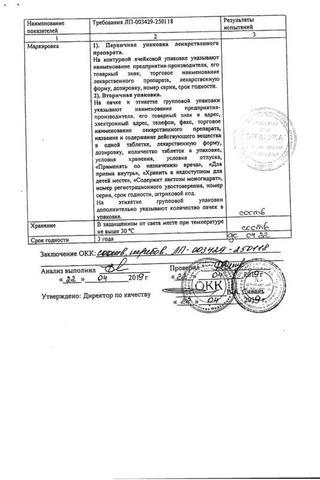

Аллопуринол таблетки 300 мг 30 шт

Аллопуринол: Состав

Таблетки белого или белого с желтоватым оттенком цвета, круглые, плоскоцилиндрические, с риской и фаской.

1 таб.

аллопуринол 100 мг

Вспомогательные вещества: целлюлоза микрокристаллическая (МКЦ-101 Премиум) - 54 мг, крахмал кукурузный - 25 мг, карбоксиметилкрахмал натрия - 10 мг, повидон К25 - 8 мг, кремния диоксид коллоидный - 1 мг, магния стеарат - 2 мг.

10 шт. - упаковки ячейковые контурные (1, 2, 3, 4, 5, 6, 7, 8, 9 или 10 шт.) - пачки картонные.

14 шт. - упаковки ячейковые контурные (1, 2, 3, 4, 5, 6, 7, 8, 9 или 10 шт.) - пачки картонные.

25 шт. - упаковки ячейковые контурные (1, 2, 3, 4, 5, 6, 7, 8, 9 или 10 шт.) - пачки картонные.

30 шт. - упаковки ячейковые контурные (1, 2, 3, 4, 5, 6, 7, 8, 9 или 10 шт.) - пачки картонные.